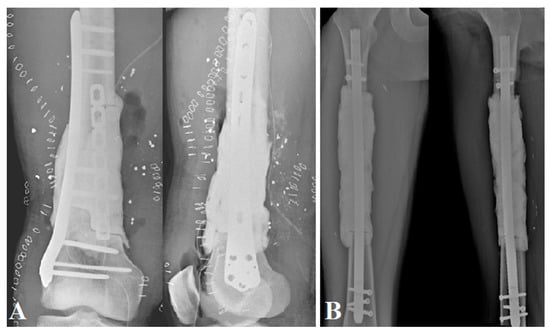

The two patients with bone tumors underwent initial oncologic resection; the other patients had post-traumatic septic lesions that required debridement, irrigation, bacteriological sampling, and antibiotic therapy. The femur was prepared with a clear, clean cut in a healthy zone, if necessary, either transversally (n = 3) or in step-cut (n = 1). The aim of this first step was to model a cement spacer using high-viscosity Heraeus Palacos® R + G cement (Hanau, Germany); it has to fill the bone loss as fully as possible. We preferred to oversize it somewhat in width if the soft tissue coverage was not an issue, as it increases reconstruction space and facilitates induced membrane closure for the second stage. The spacer was needed to cover the bone–host interfaces as recommended in the Masquelet technique []. It was enhanced on a locked intramedullary nailing, positioned back and forth (n = 3) or on a plate (n = 1) (Figure 1).

Figure 1.

Postoperative X-ray AP and lateral view of the spacers: (A) a plate-enhanced spacer on a bone defect with step-cut in setting a septic ballistic trauma of the right distal femur (patient No. 4); (B) an intramedullary nail-enhanced spacer on a bone defect after an Ewing sarcoma resection.